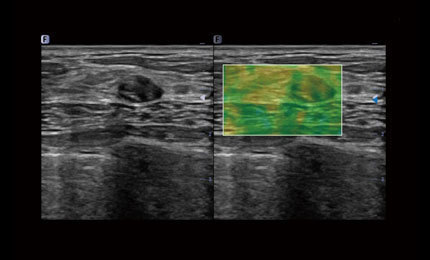

Elastography

Real time elastography is a new noninvasive and painless technique that can help determine the hardness of organs and other structures such as breast, thyroid. Elastic imaging provides users with dynamic visual information and displays the rigidity of organs, which is helpful for direct and quantitative diagnosis and treatment.